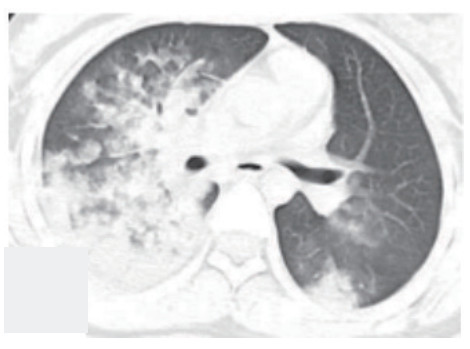

1 病例资料病例1:患者,女性,14岁,因“气急2 h”于2019-6-29入院。患者于2019年6月29日在杭州某医院行全麻下妇科手术,手术过程顺利,术中补液1 L(100 min输注500 mL胶体液+500 mL晶体液)。术后患者苏醒拔除气管插管,术后返回病房。拔管后0.5 h患者突发持续2 min的喉鸣和呃逆,之后迅速出现胸闷气急,血氧饱和度进行性下降到72%,伴有咯大量粉红色泡沫痰。立即予以高流量吸氧、速尿20 mg静注、西地兰0.2 mg静注治疗,8 min后症状略有所好转,血氧饱和度上升到97%,立即转送本院。体格检查:体温36.2℃,血压101/57 mmHg(1 mmHg=0.013 kPa),脉搏120次/min,呼吸22次/min。口唇不发绀,右肺叩诊浊音,双肺呼吸音粗,右下呼吸音低,右肺闻及较多细湿啰音;心率120次/min,律齐,无杂音;下肢无水肿。血白细胞4.7×109/L,中性粒细胞86.9%,血红蛋白155 g/L,C反应蛋白1 mg/L;N端脑钠肽前体(NT-proBNP)255 pg/mL;血浆乳酸5.4 mmol/L;生化:白蛋白34.7 g/L, 球蛋白19.3 g/L,余正常。胸部CT显示两肺大片渗出及实变影,以右肺为主,伴有右上叶小叶间隔增厚(见图 1)。入院诊断:负压性肺水肿。入院后予以速尿20 mg静注一次和甲基强的松龙40 mg静注一次,同时高流量吸氧,患者术后第2天后症状明显改善,术后第3天完全消失,术后第4天复查肺部CT病灶完全吸收(见图 2)。

| 图 1 病例1术后当天胸部CT |